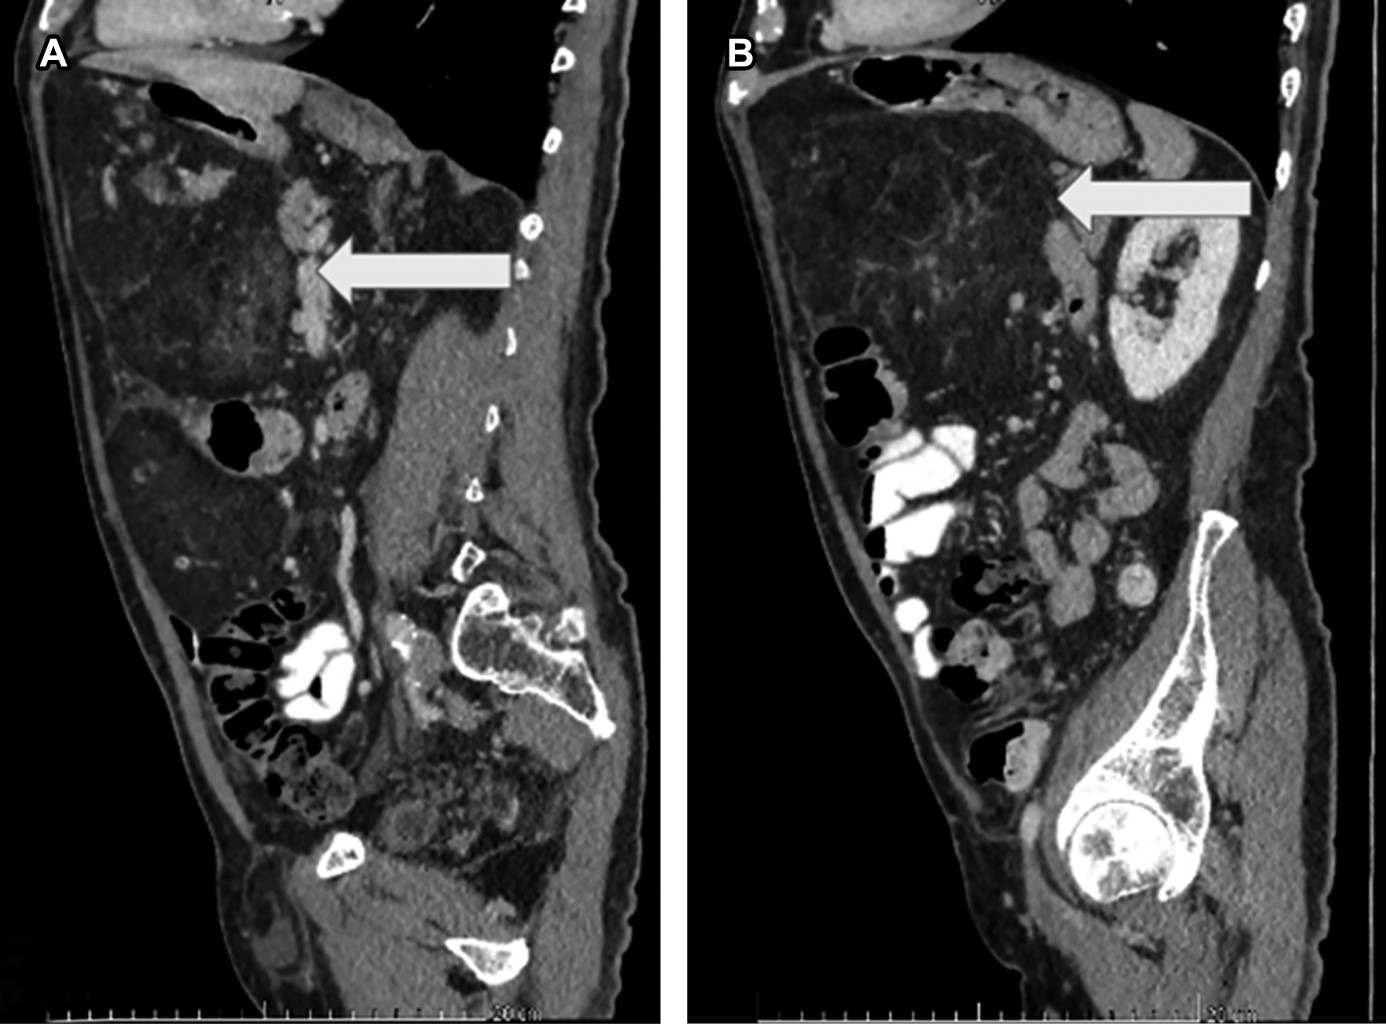

Se trata de paciente masculino de 68 años con antecedente de adenocarcinoma acinar poco diferenciado de próstata en etapa clínica I, tratado con prostatectomía por robot sin terapia adyuvante, cuatro meses después presenta distensión y dolor abdominal tipo cólico, intermitente, de intensidad leve, por lo que acude a urgencias. Se solicita TAC de abdomen (Figura 1), las imágenes eran compatibles con un liposarcoma, por lo que se procede a realizar laparotomía exploratoria. Al abrir se observa tumoración (Figura 2) y se realiza disección con energía avanzada, se observa gran tumor de 45 × 38 × 18 cm, desplazando todas las vísceras hacia la derecha (Figura 3), se efectúa cirugía R0 (cirugía sin tumor macroscópico residual) realizando resección de tumoración lipomatosa retroperitoneal sin otra estructura adyacente. No se realizó resección de colon. Tuvo una adecuada recuperación y se decide su egreso a los ocho días postoperatorios, con seguimiento en consulta externa sin presentar alguna eventualidad.

Figura 1